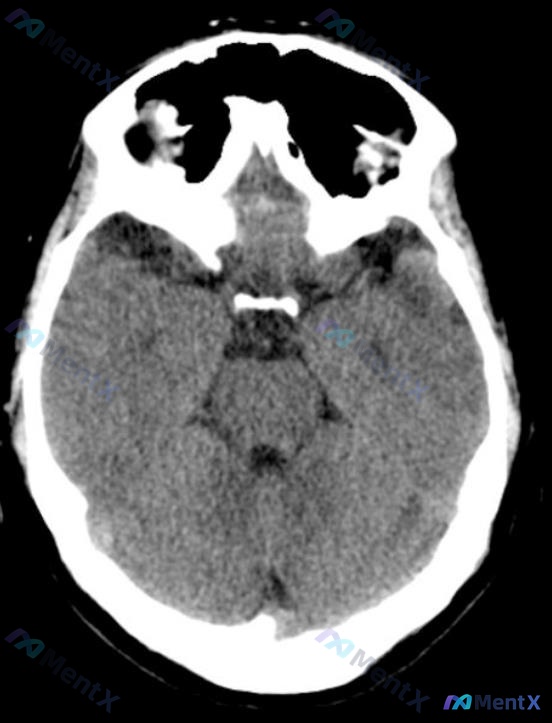

- 影像:头部CT平扫(图A)未见明显异常(灰白质分界清、无出血/占位/梗死、中线居中、基底池清晰)